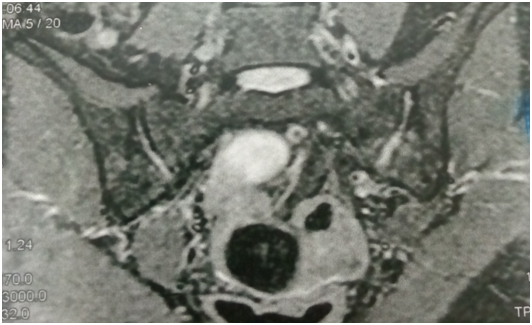

Radiological changes in the form of SIJ destruction/sclerosis (x-ray, CT) were evident in 10 of the 13 patients. MRI evidence of SIJ infection was noted on STIR sequence images in all 13 patients. The pathogens isolated were Staph. aureus in 69% (9 patients), streptococci in 23% (3 patients), and E.coli in 7% (1 patient).

MRI represents the most sensitive and specific method in early diagnosis of infectious sacroiliitis. The short tau inversion recovery sequence (STIR) was found to be more effective than the T1 contrast-enhanced sequence, particularly in delineating all findings of the SI joint inflammation and allowing for the early detection of septic sacroiliitis.2

Figure 2 left SIJ showing low signal intensity (edema and suppuration) and irregular joint outline (denoting destruction) on T1 MRI.